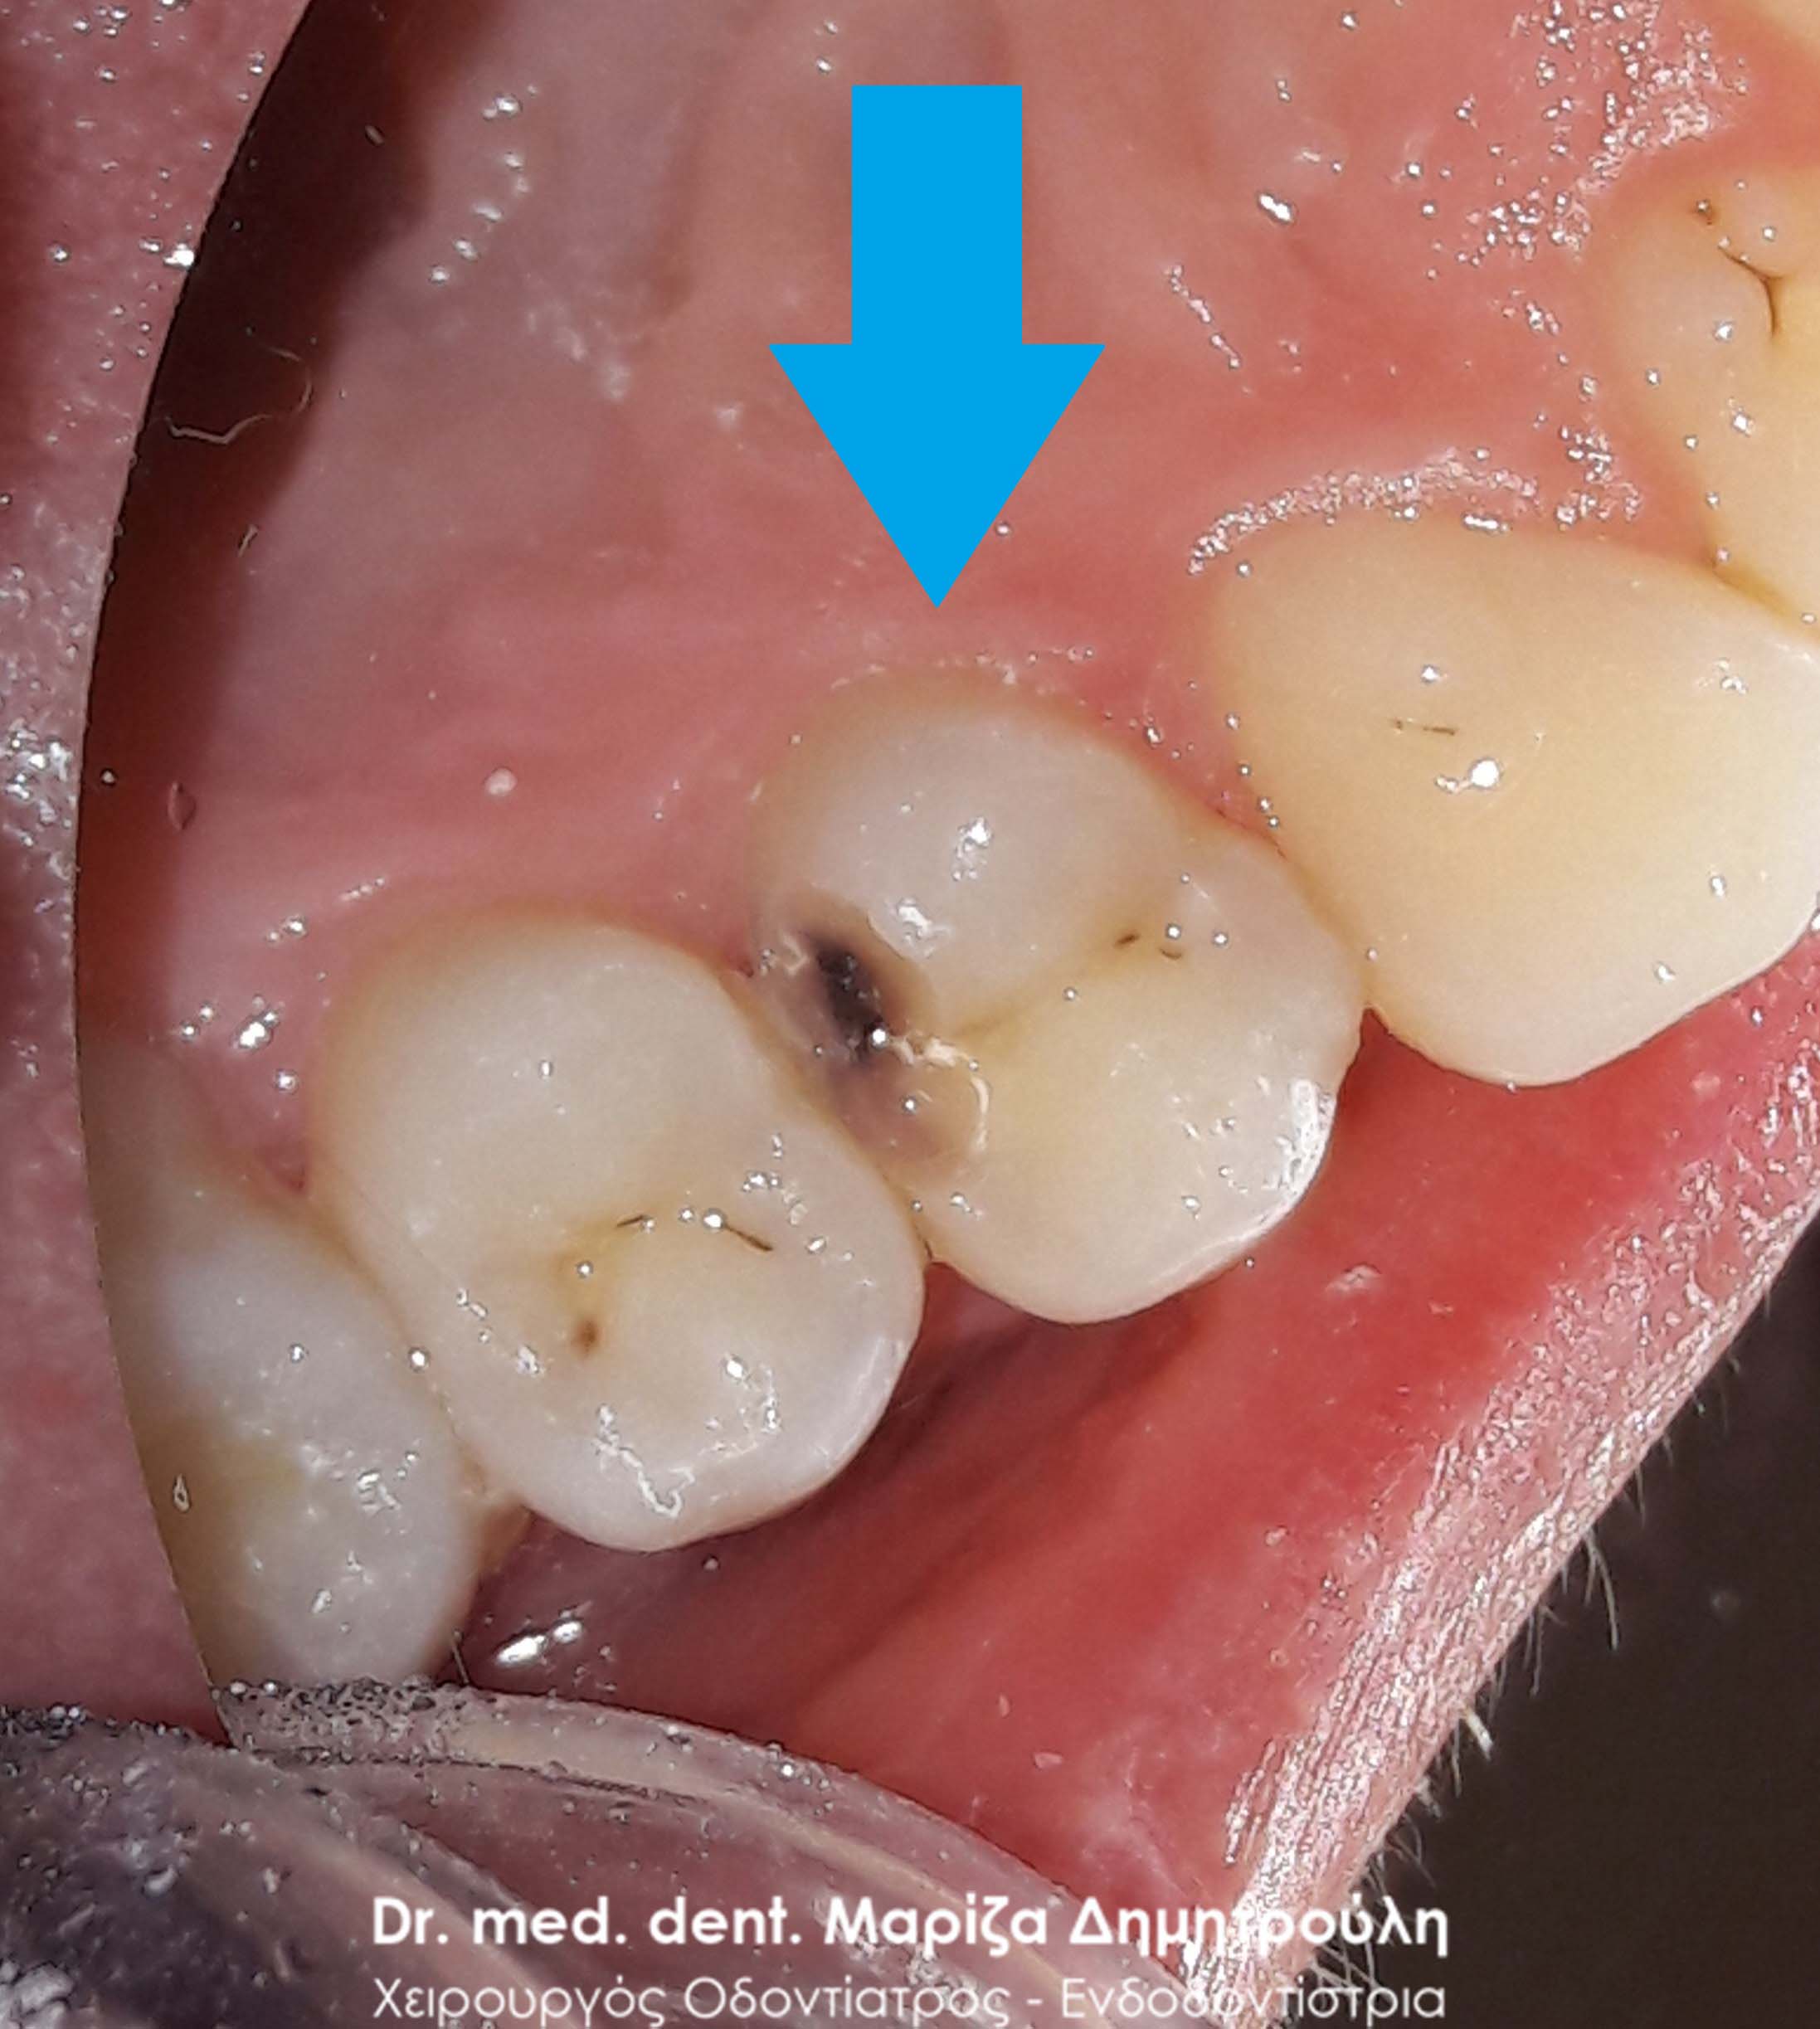

Στα πλαίσια του ετήσιου οδοντιατρικού ελέγχου εντοπίστηκε ένα τερηδονισμένο δόντι, το οποίο δεν είχε γίνει αντιληπτό από τον ασθενή. Προτού ξεκινήσει η διαδικασία τροχίσματος του δοντιού, ο ασθενής ενημερώθηκε οτι η τερηδόνα πιθανόν να εκτείνεται βαθιά (στο ύψος του νεύρου του δοντιού), γεγονός που επιβεβαιώθηκε κατά τη διάνοιξη της κοιλότητας (2η φωτογραφία). Η αποκατάσταση του δοντιού πραγματοποιήθηκε με λευκό σφράγισμα ρητίνης.

ΠΡΙΝ

Εικόνα της βαθιάς τερηδονικής κοιλότητας του δοντιού

ΜΕΤΑ